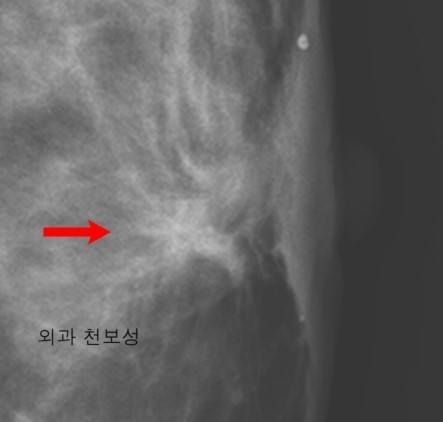

유방암에 대한 정기검사는 국가암검진 권고안에 의하면 40세부터 2년에 한 번씩은 유방촬영술을 자주 하는 것이 탁월하다고 생각해요. 또한 자가 검진은 한 달에 한 번씩 생리 끝나고 대략 1주일 정도 되었을 때가 가슴이 가장 작아져 있을 때 하는 것이 좋아요. 한 달에 한 번씩 자가검진을 통하여 혹시 만져지는 종물은 없는지 멍울이 있지 않는지 관찰을 해보고 혹시라도 체크 이 된다면 진료를 받는 것을 추천드려요.